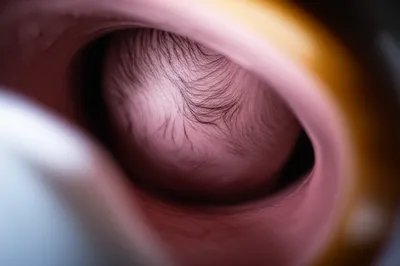

verb Скачать 🔗Поделиться Представляться To appear (in a specific way) for delivery (of a fetus); to appear first at the mouth of the uterus during childbirth. Examples : "During labor, the baby was presenting breech, meaning its buttocks were appearing first instead of its head. " Во время родов ребенок представлялся ягодицами вперед, что означало, что сначала появлялись ягодицы, а не голова. medicine physiology body sex family human Чат с ИИИгра со словамиПрактика чтения